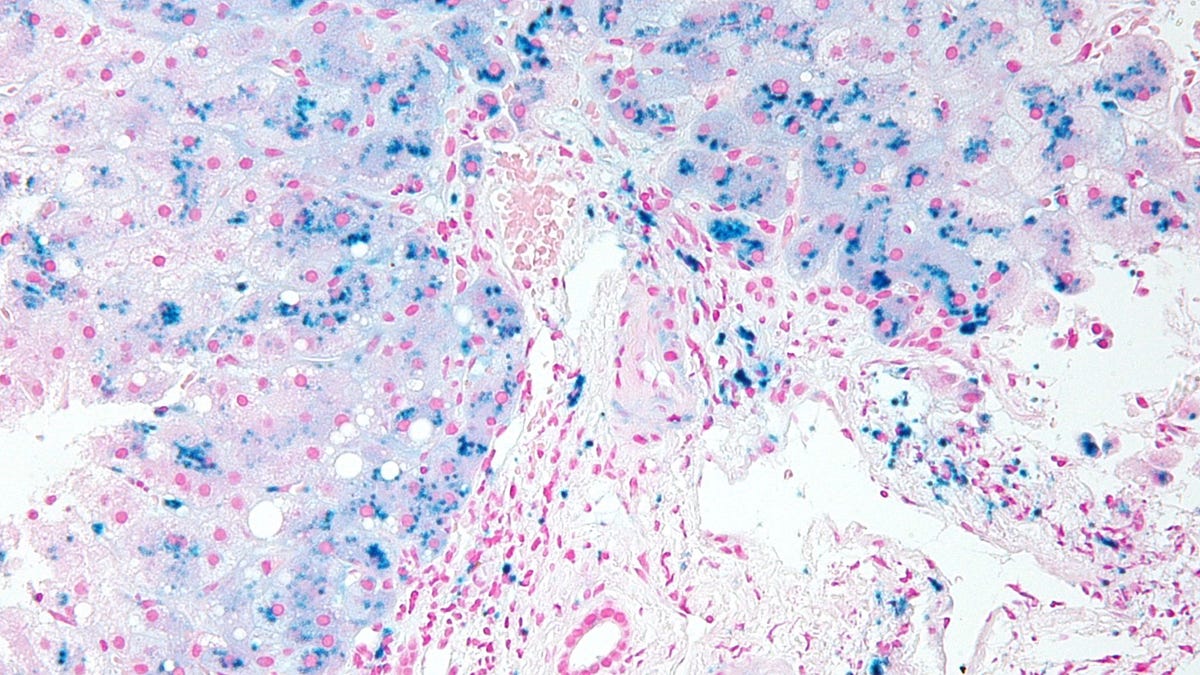

The genetic disorder that turns the body into an iron trap